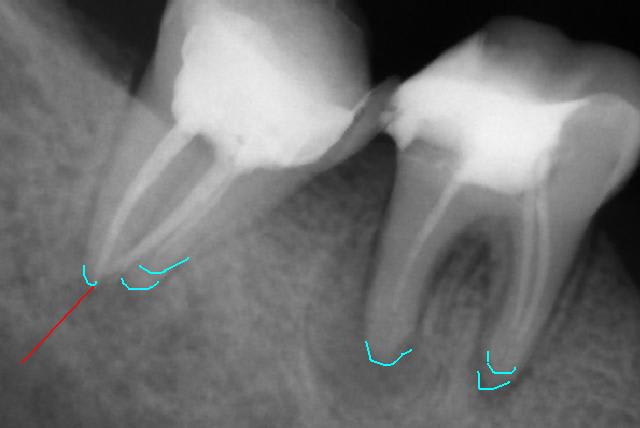

J'arrive bien à voir des choses mais impossible de copier l'image pour remettre des annotations dessus.

voici ce que je vois

Sans titre is8zr9 - Eugenol